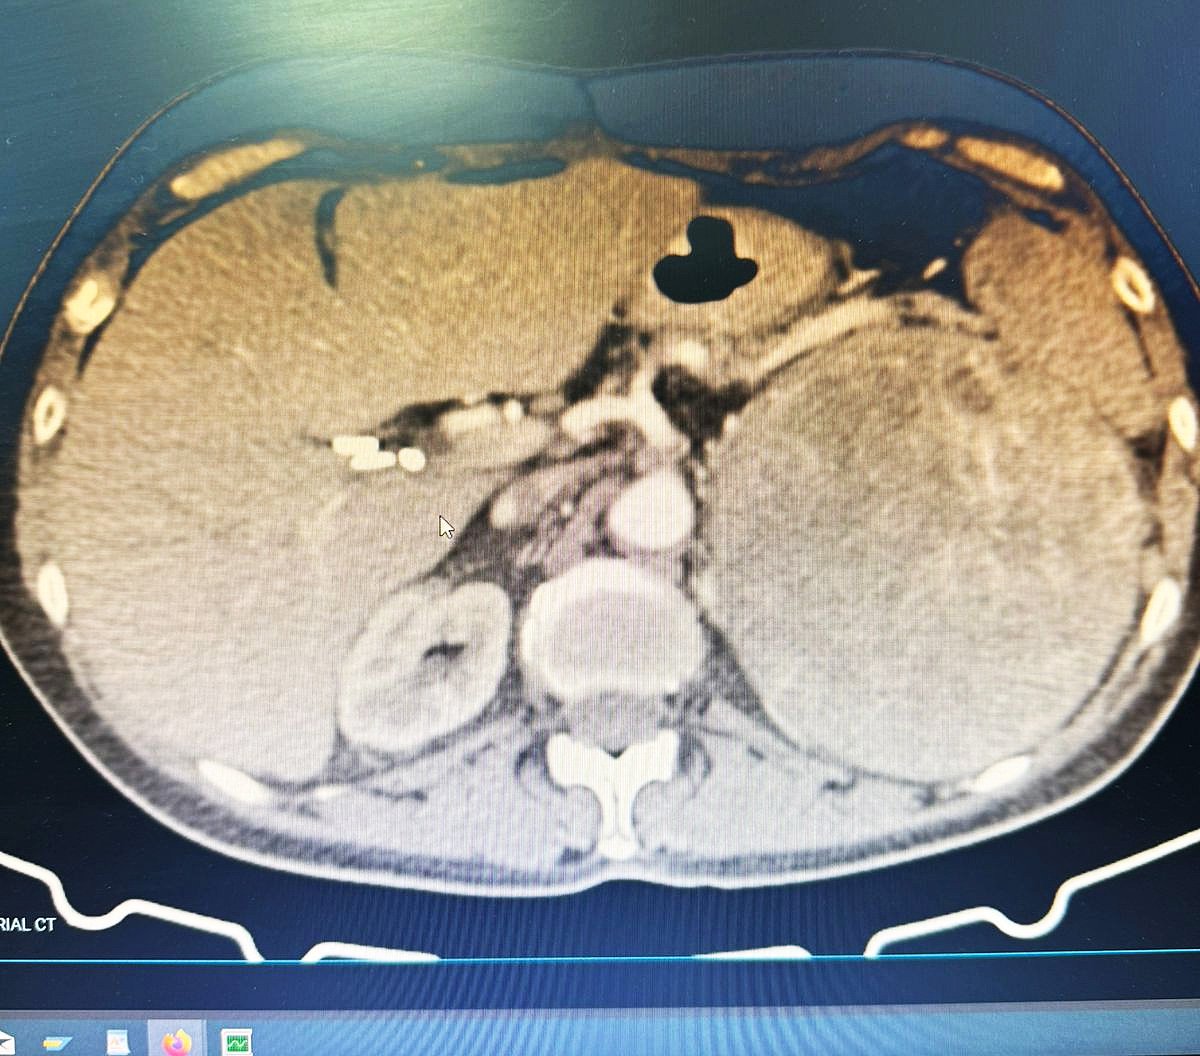

La profesional señala que este caso fue muy desafiante por la alta dificultad que presentó, debido al tamaño del tumor que fue de aprox. 25 cm de diámetro mayor y estaba adherido a otros órganos importantes y a múltiples arterias y venas de diferentes calibres que irrigaban al tumor.

El hallazgo operatorio fue de un tumor suprarrenal izquierdo de aproximadamente 25 cm de diámetro mayor, duro, elástico, de bordes regulares y bien delimitados, hipervascularizado, firmemente adherido al polo renal izquierdo, al parietocolico izquierdo, al hilio esplénico y al hemidiafragma ipsilateral.